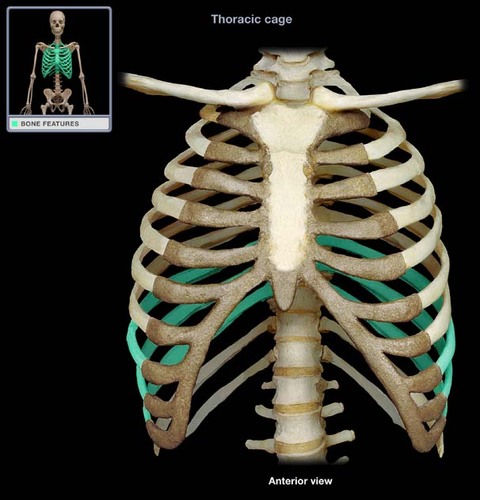

True ribs

7 pairs

False ribs

5 pairs

vertebrochondral ribs

floating ribs

costal cartilage